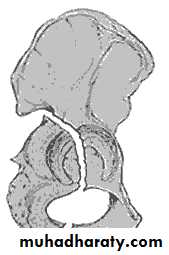

:Radiological classification

GRADE 1

:the femoral head is in its normal position or tilted into valgus and impacted on the femoral stump.

GRADE 2

The femoral head is normally placed and the fracture line may be difficult to diagnosed

GRADE 3

The femoral head tilted out of position and the trabecular marking are not in line with those of innominate bone.

GRADE 4

The femoral head trabeculae are normally aligned with those of innominate bone.